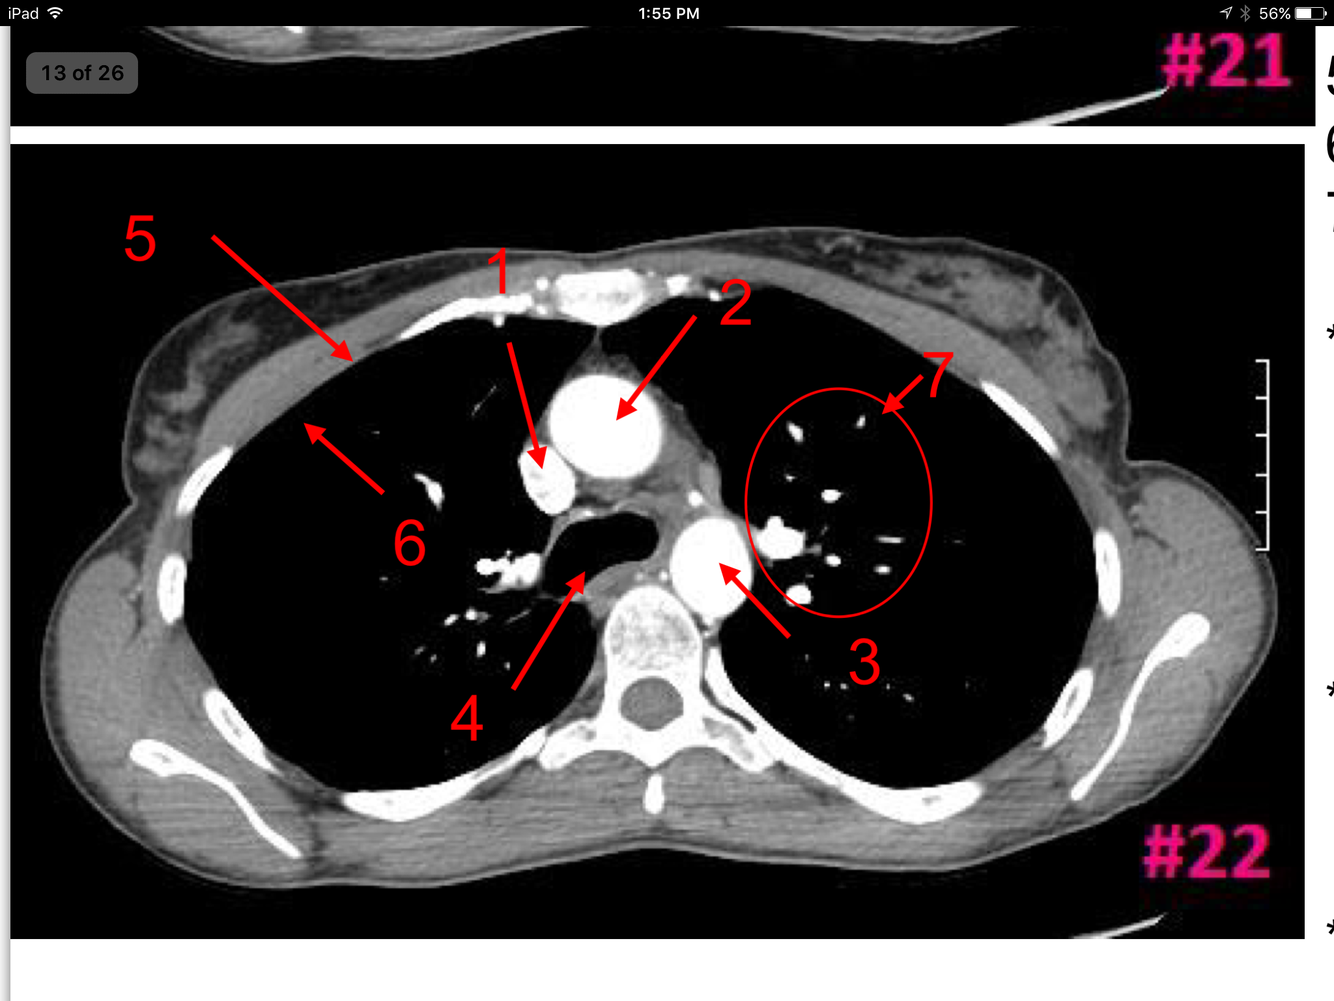

Rt atrium

Rt ventricle

Lt ventricle

Thoracic aorta

Interatrial septum

Rt atrioventricular septum

Interventricular septum

A